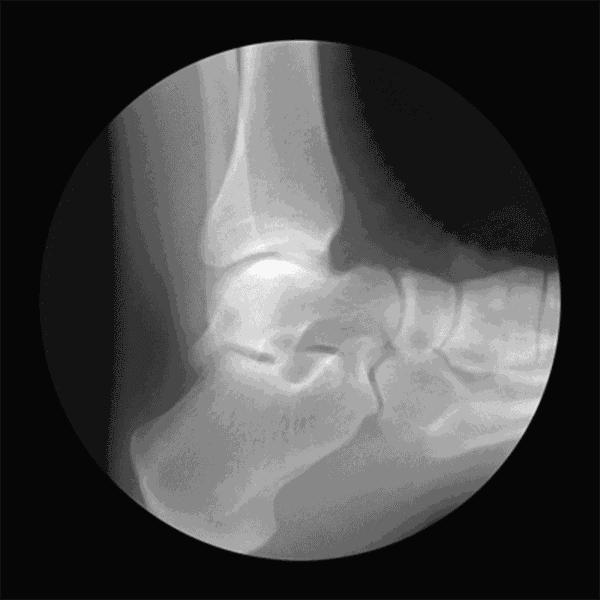

举个例子,足跟部骨刺早期确实非常疼痛,但是,一旦足跟部重新获得稳定,疼痛会好转或自行消除,可见人体是多么奇妙。